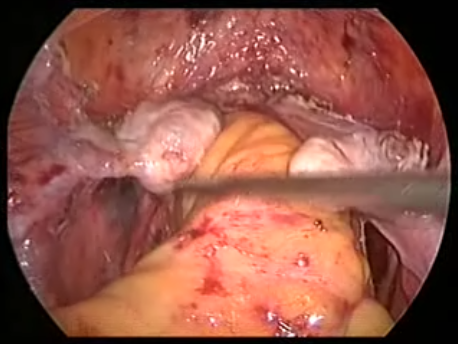

Although vaginal surgery and repair was preferred in older women, laparoscopic surgery has become the route of choice today. This is because vaginal repair utilizes already damaged tissue to repair the prolapse and, hence, the chance of failure of surgery and recurrence of prolapse over the long term is significantly higher.